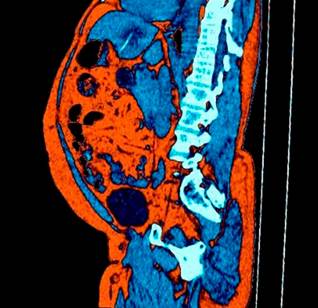

This case involves a 55-year-old male patient presenting with a one-year history of intermittent abdominal pain localized to the epigastric and left iliac fossa regions, without other associated symptoms. He denied having fever, jaundice, or ingesting any foreign body. His medical history included obesity, hypertension, and frequent alcohol consumption. He presented to our institution for an abdominal ultrasound, which identified a liver abscess in segments II and III containing a foreign body, along with inflammatory changes in the fat of the gastrohepatic omentum (Figure 1). Subsequently, an abdominal CT scan was requested to confirm these findings (Figure 2). The general surgery team opted for hospitalization to provide antibiotic therapy with intravenous ciprofloxacin 200 mg every 12 hours and metronidazole 500 mg every 8 hours. Admission laboratory tests indicated elevated acute-phase reactants (leukocytosis, mild neutrophilia, and C-reactive protein [CRP]), mild alteration in liver enzymes (aspartate aminotransferase [AST]: 52.3 U/L and alanine aminotransferase [ALT]: 23.3 U/L), with bilirubin levels, alkaline phosphatase, and coagulation times within normal limits.